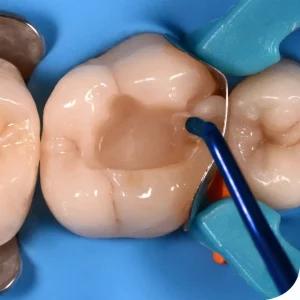

Mouth Mirror Tops are used by the dentist or dental auxiliary to view a mirror image of the teeth in locations of the mouth where visibility is difficult or impossible. They also are used for reflecting light onto desired surfaces, indirect vision, and retraction of soft tissues to improve access or vision. A mouth mirror is the most common instrument used in dental clinics, as a diagnostic instrument.

- Used in the field of Dentistry.

- Used for Illumination.

- Used for retraction.

- Used for visualization.

- Used for Transillumination.